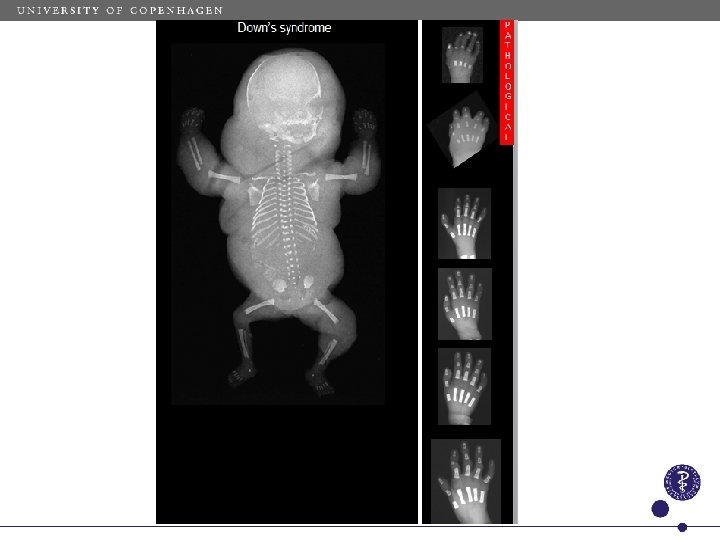

Trisomy 21